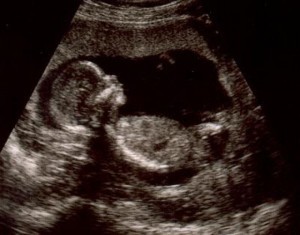

Развитие человека от момента оплодотворения до рождения — один из самых сложных и тонко организованных процессов в биологии. Всего за 38 недель одна-единственная клетка превращается в многоклеточный организм, состоящий из более чем двухсот типов клеток, органов и систем, работающих согласованно. Благодаря современным методам визуализации сегодня можно увидеть, как постепенно формируется будущий человек и какие удивительные этапы проходит эмбрион. Это путешествие в мир внутриутробного развития позволяет лучше понять, как работает человеческое тело, и осознать, какие точные механизмы лежат в его основе.

К 14-й неделе плод достигает примерно 14 сантиметров. Укрепляются костные структуры, пальцы рук и ног полностью разделены, формируется мимика и движение глаз. Мозг координирует всё больше процессов, и плод начинает активно исследовать пространство — движениями, реакцией на свет и звуки.

К 24 й неделе шансы на выживание при преждевременных родах значительно повышаются благодаря современным технологиям ухода. В последние месяцы плод активно растёт, совершенствует органы чувств, реагирует на свет, голоса и музыку.